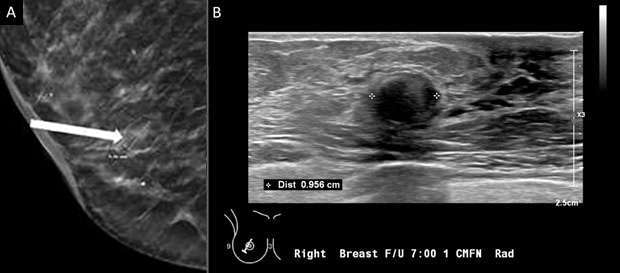

1. Oval: an oval mass (Figure 1) is elliptical or egg-shaped (may include two or three undulations).

Mammography: Masses Figure 1

Figure 1: Targeted ultrasound examination of the right breast demonstrated an oval mass with circumscribed margins measuring 7 x 4 x 7 mm seen at 3 o'clock located 2 centimeters from the nipple. Oval mass is probably benign, sonographic follow-up in 6 months is recommended. BI-RADS Category 3: Probably Benign Finding.